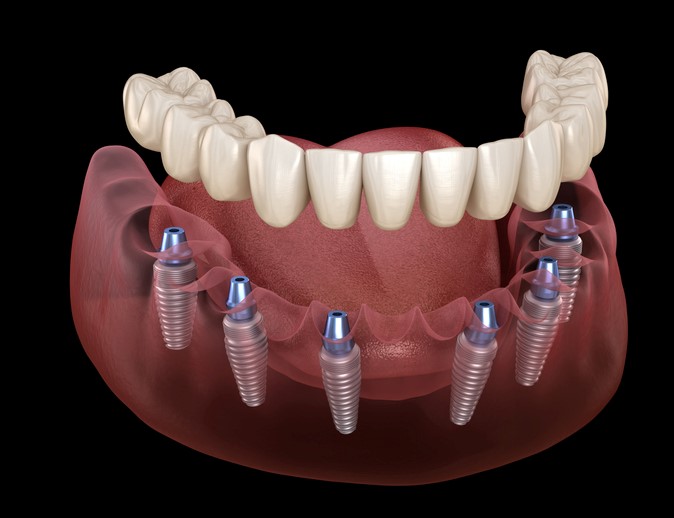

What are All-on-6 Dental Implants?

All-on-6 dental implants are a type of full-arch restoration for patients who have lost most or all their teeth. It involves placing six dental implants in the jawbone to support the complete upper or lower teeth set. The name “All-on-6” refers to using six implants per arch to support a fixed, non-removable bridge of teeth.

The All-on-6 dental implant technique is designed to provide patients with a more comfortable, stable, and functional alternative to traditional dentures. The six implants are strategically placed in areas of the jawbone with sufficient bone density and volume to support the implants.

Overall, All-on-6 dental implants can be a good option for patients who have lost their teeth and are looking for a more permanent and stable solution than traditional dentures.